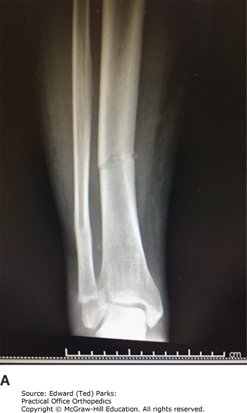

Tibia and Fibula (Tib-Fib) Fracture on X-ray

An AP (A), and lateral (B) x-ray of a tibia and fibula (tib-fib) fracture demonstrating how the fracture can appear well aligned on one view and displaced on the other. When getting x-rays to evaluate an injured extremity, it is important to obtain at least two views at 90 degrees.